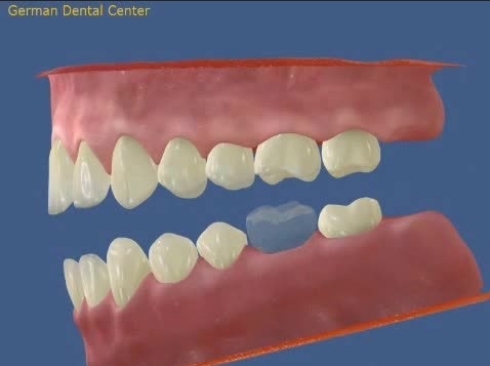

- Исправление прикуса

- Протезирование